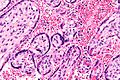

English: Very high magnification micrograph of maternal malaria. Placenta. H&E stain.

The images show organisms within the red blood cells. Related images

Chorionic villus.

Syncytiotrophoblast.